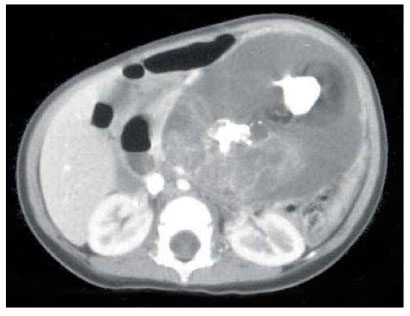

An 18-month-old girl was transferred to our hospital due to a large left upper abdominal mass, found incidentally while bathing. She had no associated complaints. On physical examination, an approximately 11 cm well-defined, firm, movable globular mass was palpated in the left upper quadrant of her abdomen. Her serum α-fetoprotein (AFP) concentration was elevated to 950 ng/mL (normal, < 8 ng/mL), whereas other biochemical parameters and tumor markers, including carbohydrate antigen (CA) 125 and β-human chorionic gonadotropin (β-hCG) were within normal limits. Abdominal ultrasonography (USG) showed a huge cystic mass with multiseptation, calcification, and solid components in the left upper quadrant of the abdomen. Abdominal computed tomography (CT) scanning revealed a 12 × 8 cm, well demarcated, cystic mass with calcification and solid and fat components in the left upper quadrant of the patient's abdomen, along with a 1 cm, well-defined, ovoid, low density nodule in segment IV of her liver (

Fig. 1Abdominal CT scan in our patient, showing a 12 × 8 cm, well-demarcated, cystic mass with calcification and solid and fat components in the left upper quadrant of the abdomen.